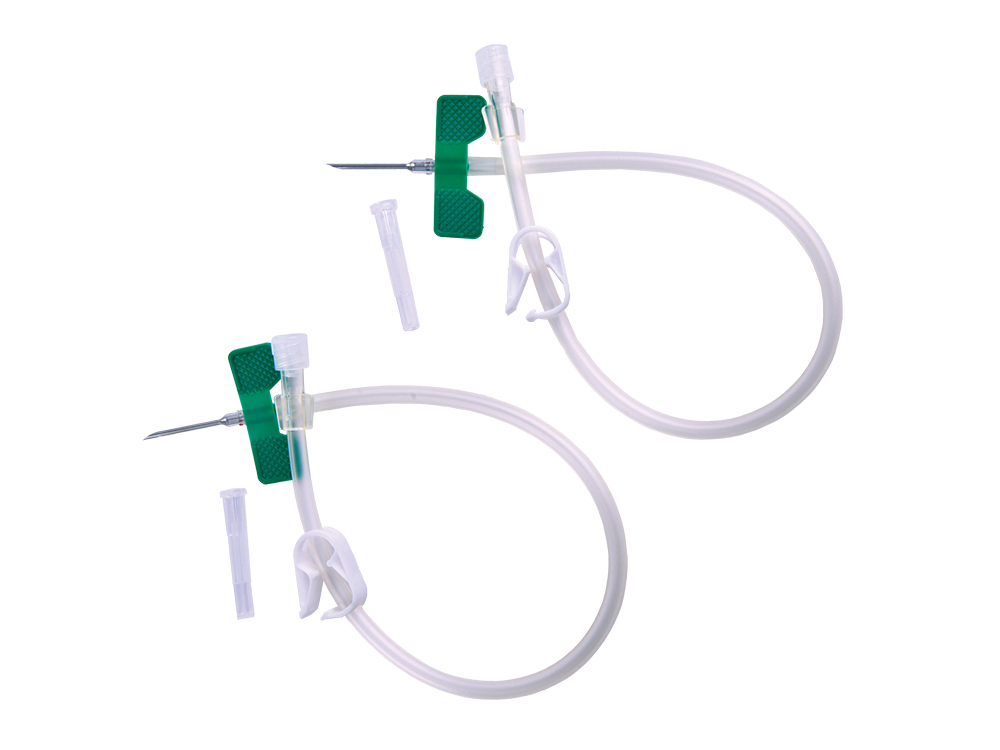

JXXD0777 Hemodialysis Blood Collection Needle

Fistula Needles (14G-17G): Ultra-thin walls for maximum bloo...